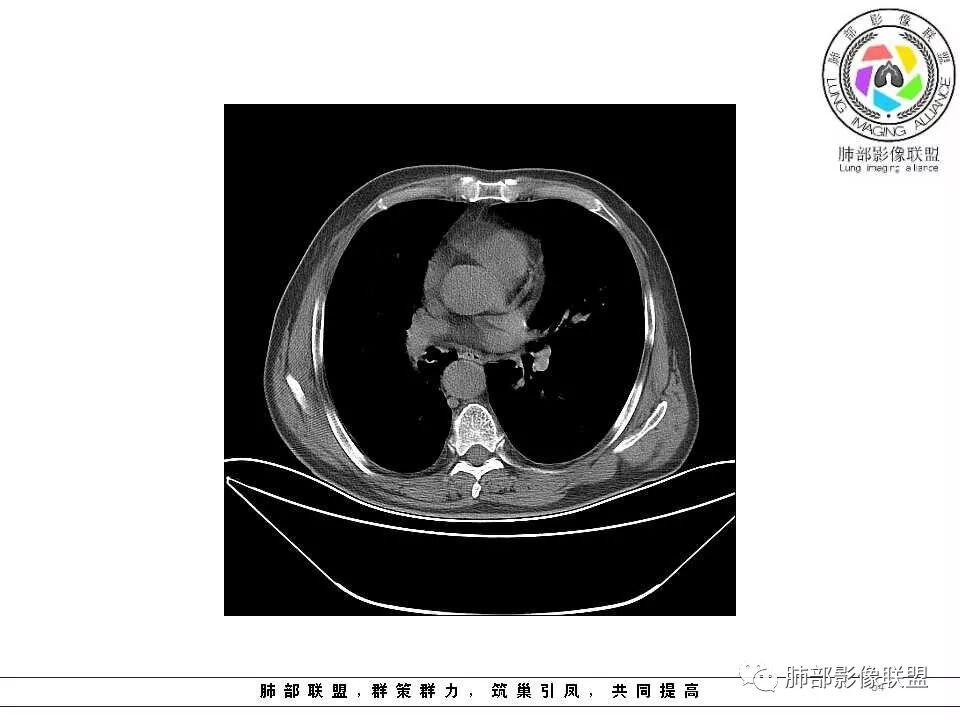

影像学特点:肺气肿背景下在大概一年的时间里出现了一个光滑的小结节,因为图像给的不是太薄,与支气管的关系判断不清,从结节周围出现斑片状炎症来判断,应该考虑结节位于支气管内,周围是阻塞性炎症,这样比较容易解释咯血

纵隔窗上似乎结节内可见点状高密度影,同时没有明显肿大淋巴结

老年男性,肺气肿基础。约一年时间出现左肺上叶舌段支气管近端结节影,远端斑片样阴影,边缘模糊。考虑近端恶性占位,远端有阻塞性炎症。

老年男性,有咳血病史,左肺上叶舌段一年时间出现新发类圆形小结节,感觉在支气管内,部分凸出气管外,没有mpr不好说,远端肺野斑片模糊影,考虑阻塞性炎症,纵隔无明显肿大淋巴结,小细胞代排,按照发展速度,类癌低度恶性,应该发展缓慢,一年病史,代排,首先考虑鳞癌并阻塞性炎症

肺气肿背景,2016年左肺上叶上舌段见微结节,一年后左肺结节增大,密度均匀,边缘光滑、膨隆,似见小分叶,下舌段片状影,沿着支气管走行,内,老年患者,咯血1月。考虑恶性病变并阻塞性肺炎,鳞癌?注意鉴别结核。

左肺上叶舌段支气管管壁略增厚 间隔一年 管壁增厚明显 向腔外突出形成结节 管腔闭塞 远端片状及斑片影 纵隔淋巴结增大 肺气肿背景 考虑鳞癌伴阻塞性炎症可能

老年男性,咯血1月,肺气肿背景,16年左肺上叶舌段结节,左肺门疑似淋巴结肿大,呈结节感。17年左肺上叶舌段见沿支气管走行分布结节 远端阻塞性肺炎,左肺门淋巴结肿大明显,首先考虑恶性病变,鳞癌?类癌?

老年男性,肺气肿背景,左肺上叶舌段一年前小结节后长大,实性,与邻近气管关系密切,远端有少许小片状炎症类小结节状,左肺门淋巴结肿大,首先考虑恶性,鳞癌可能性大,代排小细胞癌。病灶下方斑片状影,考虑炎症。

老年男性,咯血1月,肺气肿背景,左肺上叶舌段见沿支气管走行分布结节,呈葫芦样改变,左肺门淋巴结肿大明显,首先考虑恶性病变,小细胞癌可能